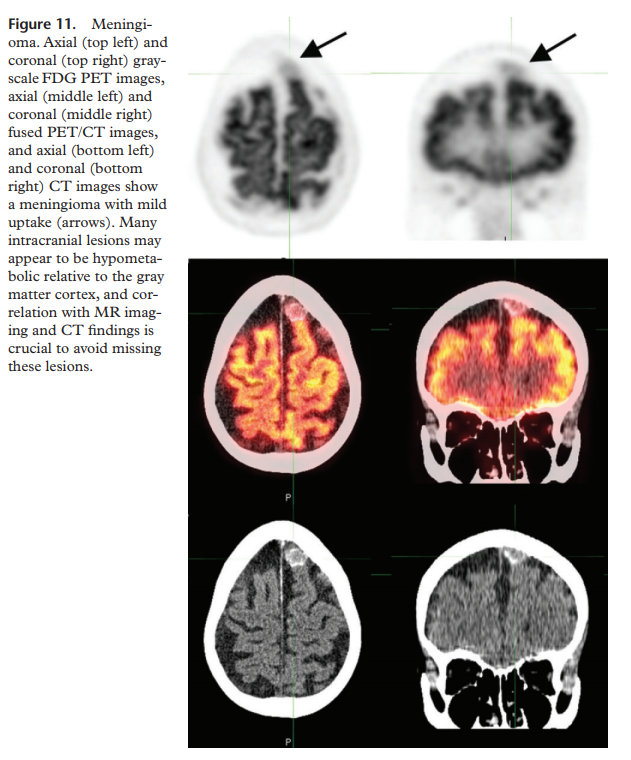

If the frontal lobe or internal capsule is involved, hypometabolism in the contralateral cerebellum may be seen due to crossed cerebrocerebellar diaschisis

misregistration due to patient motion

atrophy –> sulcal widening –> artifact of hypometabolism (pitfall for misdiagnosis of neurodegenerative disorder)